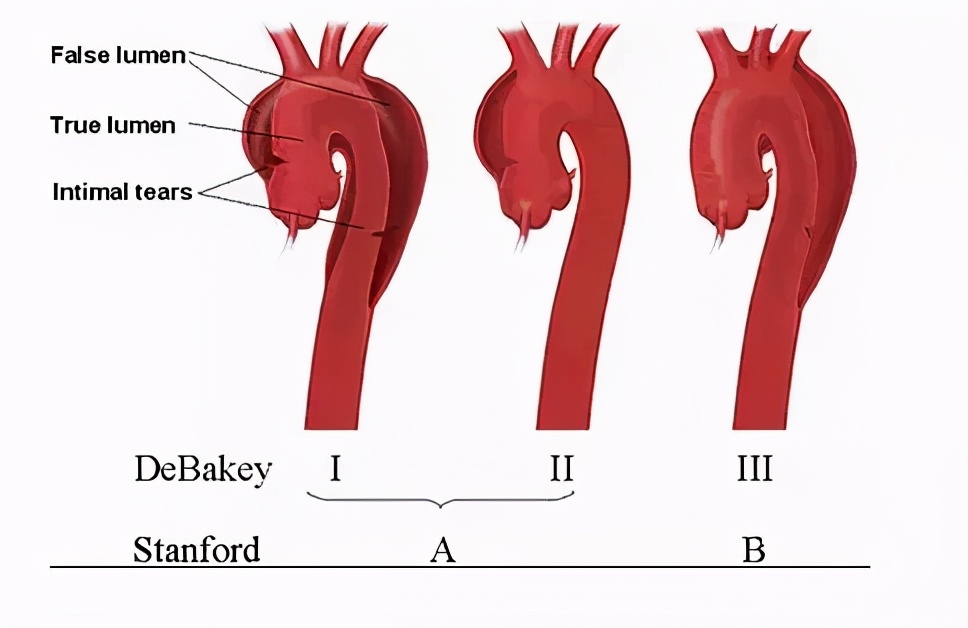

主动脉夹层的分型

主动脉弓为主动脉上部是弓形弯曲的部分。在第4胸椎下缘移行为降主动脉。从弓的凸侧发出3条较大的动脉,由右向左依次分为无名动脉(头臂干)、左颈总动脉和左锁骨下动脉。

Stanford-A:第一破口位于升主动脉、主动脉弓或近段降主动脉。夹层累及升主动脉,以及主动脉弓、降主动脉和腹主动脉。

Stanford-B:第一破口位于降主动脉,夹层仅累及降主动脉或向下延伸入腹主动脉,但不累及升主动脉。徐阿姨的主动脉夹层是Stanford-B型,如下图